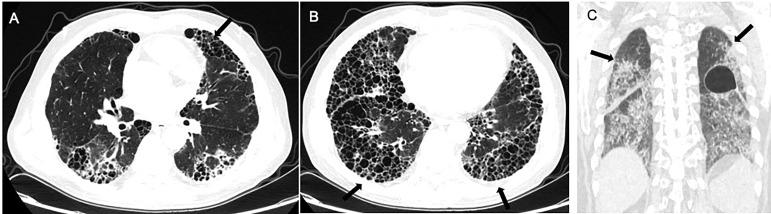

Connective tissue disease (CTD) related interstitial lung disease (CTD-ILD) is one of the leading causes of morbidity and mortality of CTD. Clinically, CTD-ILD is highly heterogenous and involves rheumatic immunity and multiple manifestations of respiratory complications affecting the airways, vessels, lung parenchyma, pleura, and respiratory muscles. The major pathological features of CTD are chronic inflammation of blood vessels and connective tissues, which can affect any organ leading to multi-system damage. The human lung is particularly vulnerable to such damage because anatomically it is abundant with collagen and blood vessels. The complex etiology of CTD-ILD includes genetic risks, epigenetic changes, and dysregulated immunity, which interact leading to disease under various ill-defined environmental triggers. CTD-ILD exhibits a broad spectra of clinical manifestations: from asymptomatic to severe dyspnea; from single-organ respiratory system involvement to multi-organ involvement. The disease course is also featured by remissions and relapses. It can range from stability or slow progression over several years to rapid deterioration. It can also present clinically as highly progressive from the initial onset of disease. Currently, the diagnosis of CTD-ILD is primarily based on distinct pathology subtype(s), imaging, as well as related CTD and autoantibodies profiles. Meticulous comprehensive clinical and laboratory assessment to improve the diagnostic process and management strategies are much needed. In this review, we focus on examining the pathogenesis of CTD-ILD with respect to genetics, environmental factors, and immunological factors. We also discuss the current state of knowledge and elaborate on the clinical characteristics of CTD-ILD, distinct pathohistological subtypes, imaging features, and related autoantibodies. Furthermore, we comment on the identification of high-risk patients and address how to stratify patients for precision medicine management approaches.